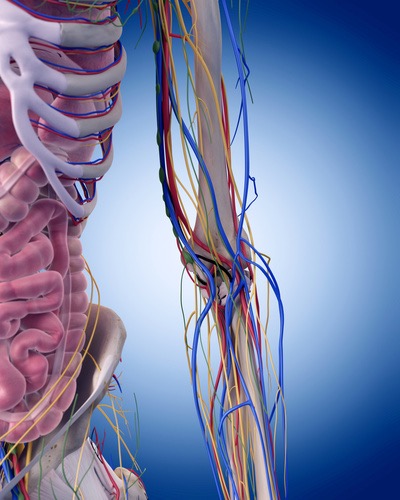

殿部~大腿部の痛みやシビレはとれたけど、膝から遠位部の神経痛がなかなか改善しないといったことは臨床でよく見られるのではないでしょうか?その原因は殿部や大腿部での神経絞扼部のリリースはできているが、この腓骨神経部のリリースができていないからなんです。遠位部の症状は慢性化することでなかなか改善されにくいと思われがちですが、それは間違いです。

この腓骨神経リリーステクニックを学ぶことであなたは、、、

脛骨神経は、坐骨神経に由来する総腓骨神経と並ぶやや径の大きな神経で、解剖学的正位で、下腿部においては、膝窩の情報で脛骨に沿って内側を走行します。下肢は坐骨神経の影響が多いと考えられていますが、実はこの脛骨神経由来の症状は臨床上とても多く経験します。特に膝窩部に部分でこの脛骨神経が絞扼されると腰痛を引き起こすことがとても多いです。

この脛骨神経のリリーステクニックを学ぶことであなたは、、、

ハンター管症候群(伏在神経麻痺)をご存知ですか?「ハンター管症候群」とは、聞きなれない疾患名ですが、まれに膝から下のふくらはぎの内側当りが痛む、しびれるという疾患があります。大腿神経の枝である伏在神経は内転筋と呼ばれる筋肉の傍を通り、ハンター管(内転筋管)と呼ばれる筋膜の管を通って、さらに下の方へと降りていきます。そして、膝の内側あたりで、膝蓋下枝と、内側下腿皮枝に分かれて、さらに下方へと伸びていきます。

膝~下腿の内側に広がる痛みやしびれは実はこの伏在神経由来の症状であることもあります。よく見逃されがちなところです。

この伏在神経のリリーステクニックを学ぶことであなたは、、、